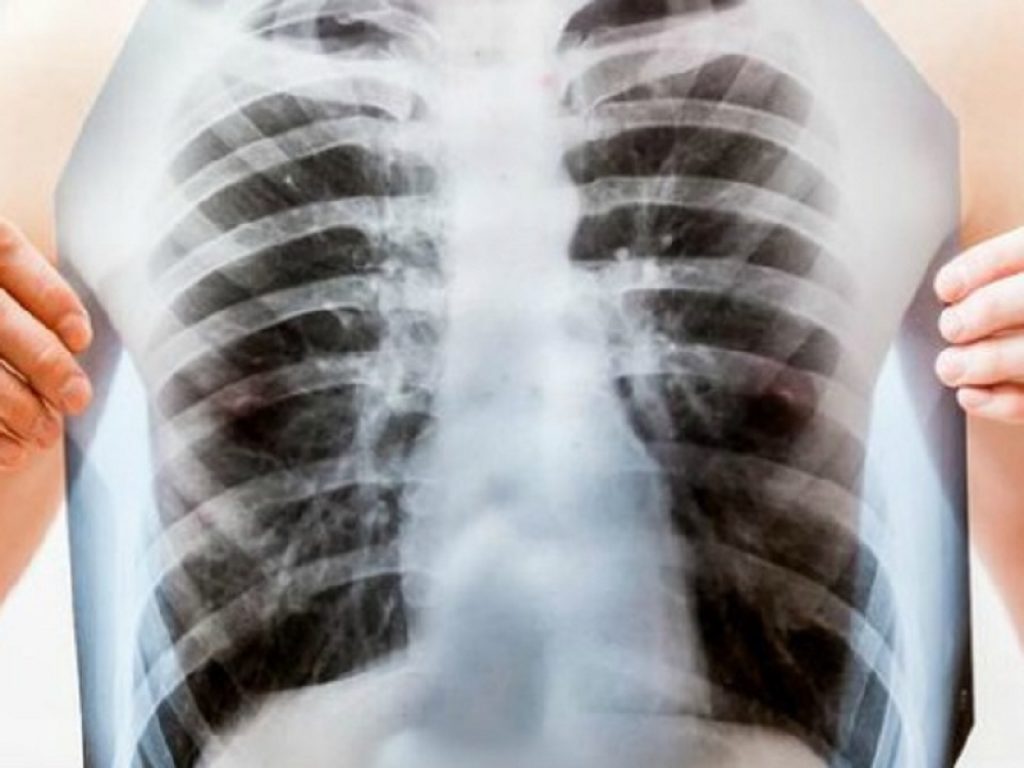

Le malattie polmonari interstiziali comprendono un ampio gruppo di oltre 200 disturbi che possono comportare la minaccia di fibrosi polmonare, una cicatrice irreversibile del tessuto polmonare che ha un impatto negativo sulla funzione polmonare.

Le persone che vivono con ILD fibrosante possono sviluppare un fenotipo progressivo, che porta al declino della funzione polmonare, al deterioramento della qualità della vita e alla mortalità precoce simile a quelli con IPF, la forma più frequente di polmoniti interstiziali idiopatiche. Il decorso della malattia e i sintomi sono simili nelle forme progressive di ILD fibrosanti croniche, indipendentemente dalla diagnosi di ILD sottostante, e si stima che tra il 18% e il 32% dei pazienti con ILD non IPF sia a rischio di sviluppare un comportamento progressivo della malattia fibrosante.